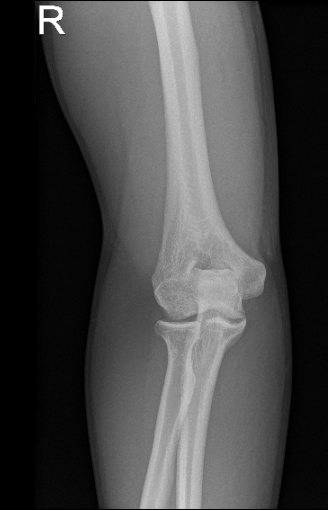

At first glance, it is suspected to have a radial head fracture. We did x-rays and found that he has a large osteophyte of the olecranon possibly secondary to chronic birth signs of the elbow.

X-ray of right elbow